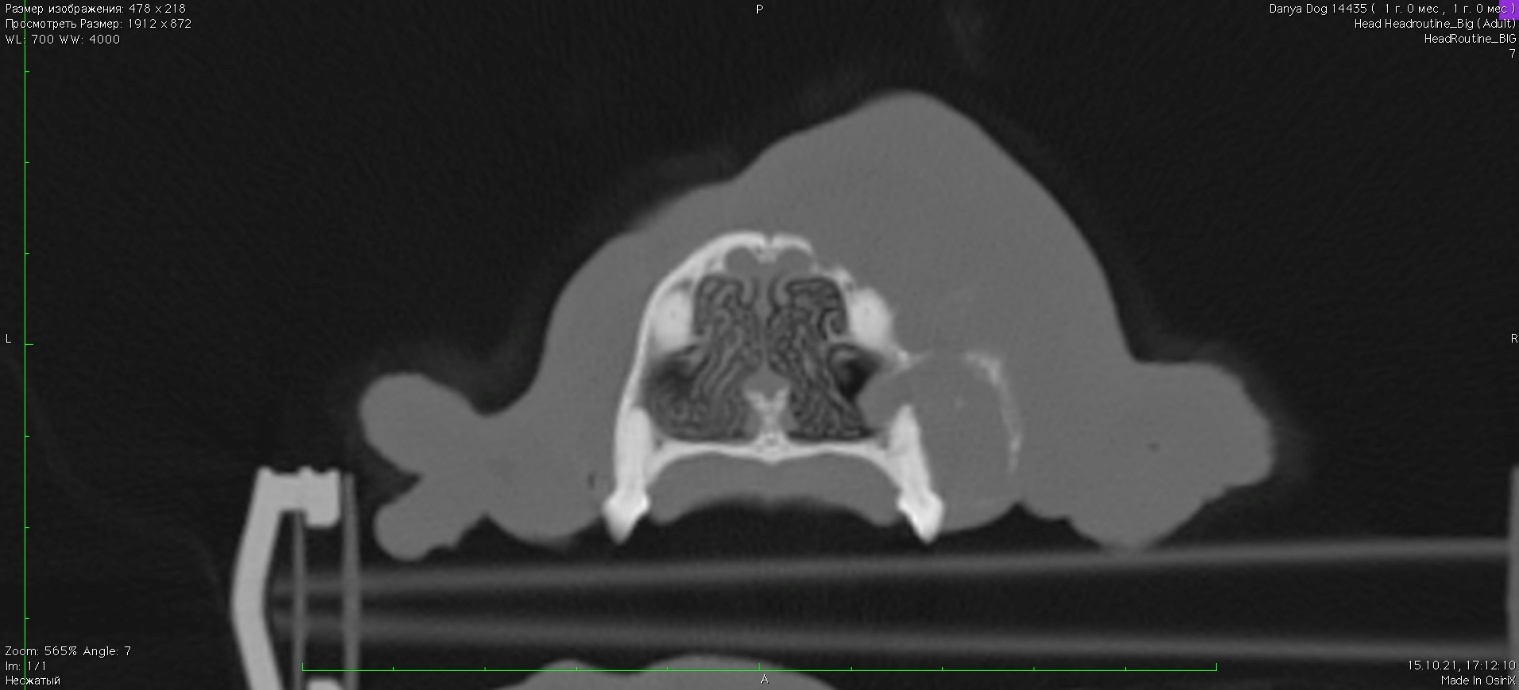

КТ исследование

Изображение 2

Отмечается частичный лизис кости верхней челюсти справа в зоне клыка и премоляров. В постконтрастную фазу отмечается очаговое образование с накоплением контраста в области верхней челюсти справа (зона клыка и премоляров) размером 17 х 25 х 17 мм. Отмечается незначительная инвазия опухоли в правый носовой ход (изоб.2).